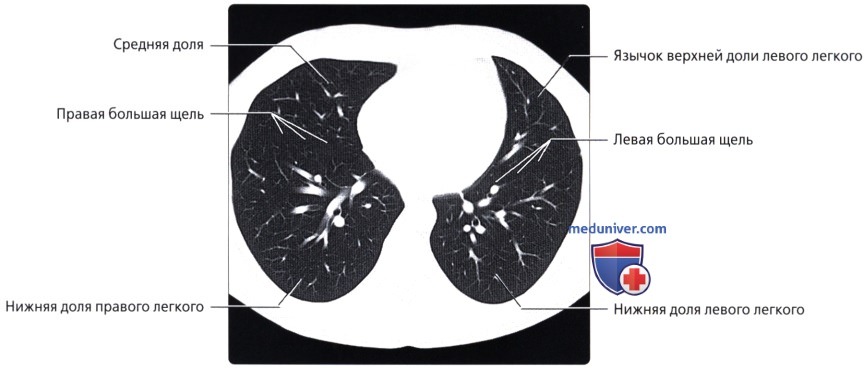

Анатомические изображения сегментов легких различных животных

Раздел: Другие животные